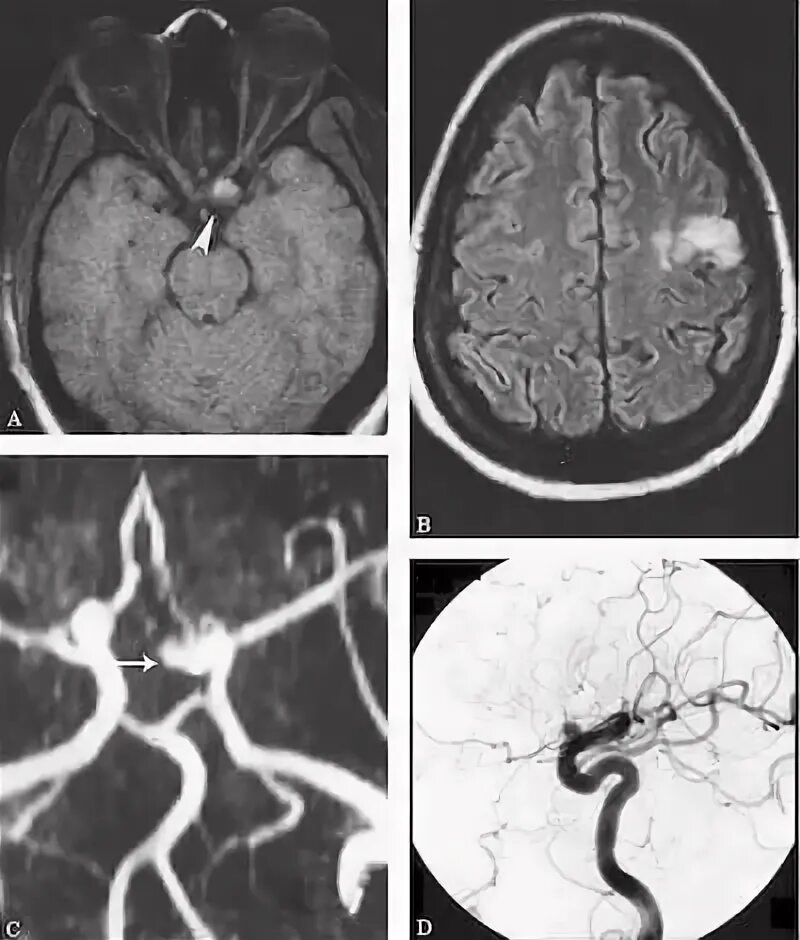

Мрт сосудов головного мозга в туле